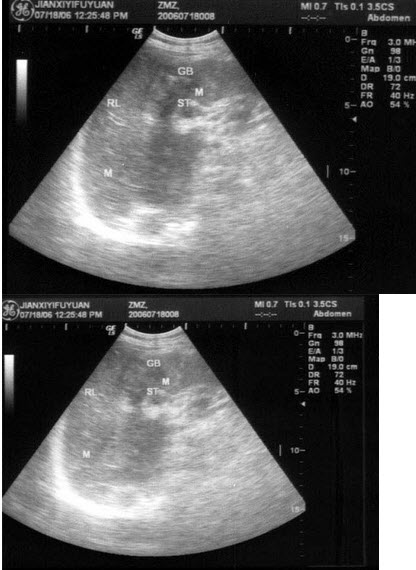

37、单项选择题

女,54岁。反复便秘,腹泻就诊。PE:左中腹可扪及一肿块,质硬,结节状,OB(Ⅱ),结合超声声像图,诊断为()

A.左肾

B.结肠癌

C.肠系膜淋巴结

D.腹膜后肿块

E.肠结核